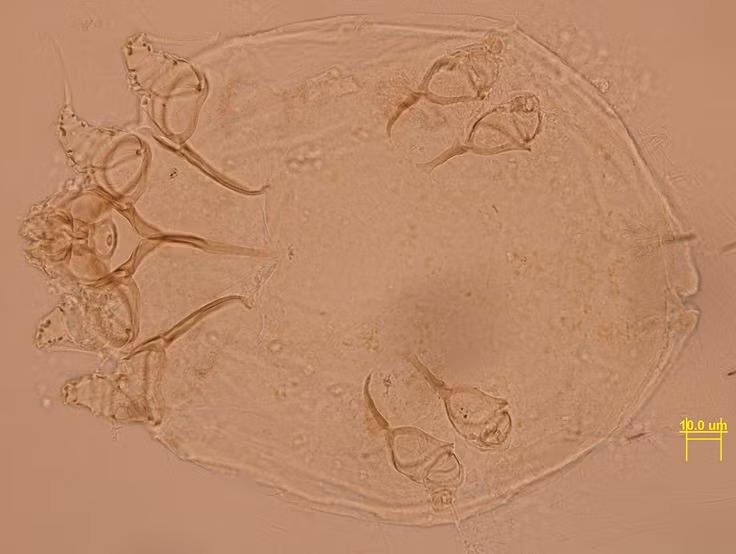

Sinh vật “tàng hình” dưới da người. Ghẻ (Sarcoptes scabiei) là một loài ve cực nhỏ, dài chưa đến 0,5 mm, gần như không thể nhìn thấy bằng mắt thường. Chúng đào hang ngay dưới lớp da, tạo nên những đường hầm li ti – nguyên nhân chính gây ngứa dữ dội. Ảnh: Pinterest.

“Kỹ sư đào hầm” đáng sợ. Con cái của loài ghẻ có khả năng đào những đường hầm ngoằn ngoèo dưới da để đẻ trứng. Mỗi ngày, chúng có thể đẻ 2–3 trứng, khiến số lượng ký sinh tăng nhanh nếu không được điều trị. Ảnh: Pinterest.